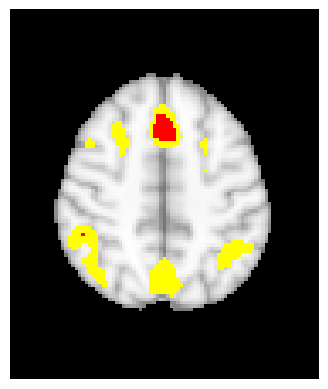

The Human Connectome Project (HCP) is a five-year study which aims to map structual and functional human brain connectivity in young adults through multiple neuroimaging modalities [van2012human]. In this section, we detail results of a real-data analysis performed on the HCP dataset with 77 participants using the confidence region methodologies proposed in this paper, as well as the method from SSS which refers to the bootstrap-based confidence region construction algorithm following Bowring (2019) [BOWRING2019116187] and SSS [SSS]. The confidence regions are built on the 77 subject-level contrast images from N-back working memory task comparing the 0-back vs. 2-back memory task. In the N-back working memory task, the participants are shown a sequence of pictures of objects and asked to remember them either immediately or 2 turns later. The image pre-processing details are presented in [glasser2013minimal, barch2013function].

5.2 Confidence Region Result

The confidence regions are constructed on fMRI scans from 77 subjects as a real data application of the proposed methods after applying additional smoothing with Gaussian kernel with FWHM to match the results shown in Bowring (2019) [BOWRING2019116187]. Confidence regions using 1) the joint method with , 2) the separate method with BH adjustment for upper and lower side each with , 3) the separate method with BH adjustment for upper side and two-stage adaptive procedure for lower with , and 4) SSS () were compared with threshold level 1.0%, 1.5%, and 2.0% Blood Oxygenation Level Dependent (BOLD) change. Joint control confidence regions are produced with instead of 0.05 for the reasons mentioned in chapter 3.

For all slices, FDR controlling methods show tighter inference of both upper and lower CR compared to the SSS method. SSS shows smaller upper CR and larger lower CR which suggests more conservative inference compared to FDR controlling testing based methodologies. This is due to the fact that by controlling for FDR, the method allows for more false discoveries in exchange for more discoveries in general. Despite having higher level at , joint control confidence regions still show comparable results to other methods even with higher significance level. Naturally, as the threshold goes up, the area enclosed between the upper and lower confidence regions decreases.